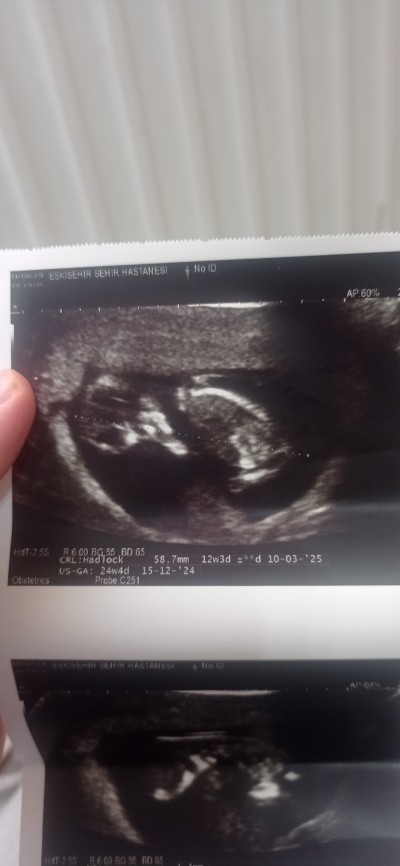

Cinsiyet tahmini bakar msnz

Tahmini veya anlayanlar

Kız diyorum.

Kıza benzettim ilk gebelikmi

İlk baş bacakalri kapalı doktor dedi genellikle kizlar kapatıp göstermiyor dedi kıza benziyor dedi 3 gün sonra gittiğimde göstermişti

Bende de sırtı dönüktü çok küçük dedi şuan benzetecek olursam kıza benziyor gibi dedi iki hata sonra gidicem benimde sol da hep oğlumda da öyleydi göğüslerim de ağrı ve sivilcelerim çıktı bunda da aynısı oldu

Crl erkek olcumu cnm ogrendinmi cinsiyetini

Kızım olacakk :)